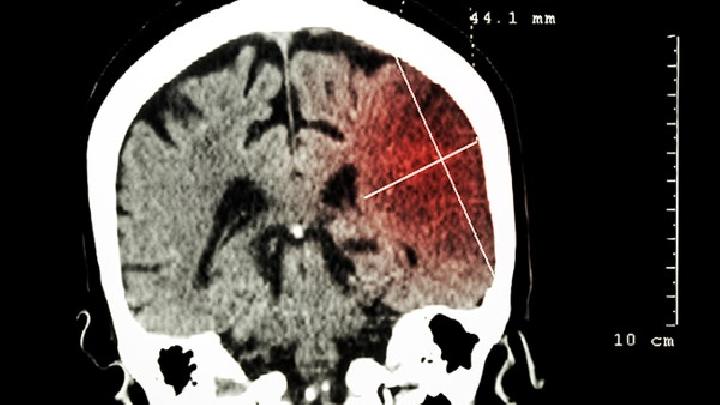

脑梗死具有发病率高、发病率高、致残率高的特点。数据显示,中国数千万家庭受到脑梗死的影响——沉重的家庭负担、高昂的医疗费用和有限的生活能力。秋季过后,天气变冷,昼夜温差扩大,脑梗死患者数量突然增加。这与温度的突然变化和温差的增加有关。因此,在秋冬季节预防脑梗死时,应注意增加衣服和保暖,适当增加运动量,多吃蔬菜和水果,少吃辛辣、刺激和油腻的食物,不要熬夜,注意休息,以防止脑梗死。对于脑梗死患者,按照医生的建议进行药物治疗对降低死亡率、提高病后生活质量至关重要。当温度变化较大时,很容易引起血管收缩和血压升高。冷热刺激也会导致脑血管痉挛血管痉挛和严重的血压波动。血管的异常收缩活动和血压的波动很容易导致斑块、血栓形成等物质的不稳定,这也可能导致脑梗死和高血压的严重运动。此外,人们还可能导致脑梗死和脑血压的运动。平时要注意观察脑梗死先兆症状的发作。当出现手麻眩晕或言语不良等症状时,应及时选择急诊医疗检查。脑梗死确诊后,西医的治疗方法包括溶栓治疗、介入手术等。随着脑梗死治疗的进展,西医疗法也发现了许多局限性和弊端。溶栓治疗必须在规定时间内进行,超过时间窗后不建议使用溶栓风险过大;溶栓也有严格的适用人群,很多患者无法接受;溶栓也有风险,患者可能有脑出血等严重并发症。手术治疗存在成本高、风险大等问题,因此现在专家们更多地关注中医治疗中脑梗死后期的恢复和治疗,以弥补西医治疗的不足和不足。从中医的角度来看,脑梗死多见于中老年人,这与中老年人体质差、气虚亏损等因素有关。中医认为气是人体的主要动力物质,通常起到促进血液运动的作用。气虚时,运动时血瘀会停止血瘀,影响血瘀、运动后血瘀、血瘀等功能。中风,即西医所说的缺血性中风。因此,脑梗死后的治疗应促进血液循环,消除血瘀,打开脑,补充气和血液,恢复气和血液的正常功能。临床常用药物脑脉利润颗粒具有促进血液循环、消除血瘀、气通络的作用,可用于气虚血瘀中风(脑梗死)急性经络期,可促进血液循环、血瘀、气通络,增强治疗效果,促进恢复,降低死亡率和致残率。